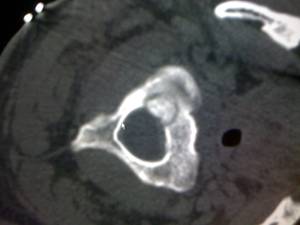

术前:VAS评分10分,CT表现齿突基底右侧占位,成骨性病变,没有明确的瘤巢。

图1:CT定位下穿刺取活检 图2:定位